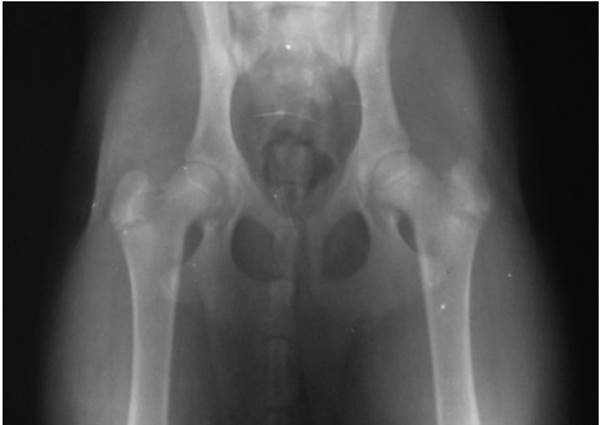

Рентгенограмма тазобедренных суставов выглядит следующим образом: